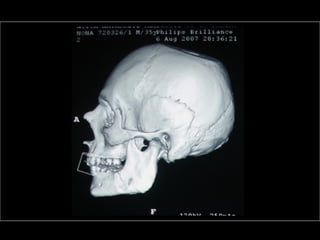

AmeloblastomaAmeloblastoma

Ameloblastoma